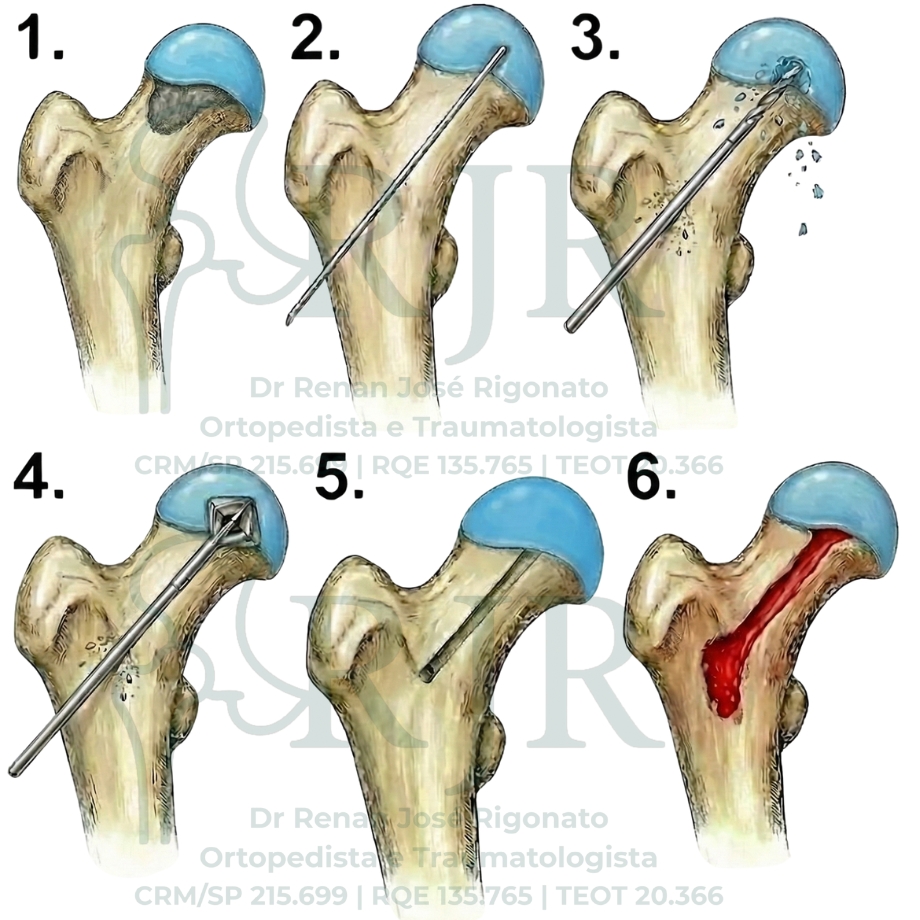

A principal opção cirúrgica nessa fase é a descompressão da cabeça do fêmur (core decompression). Esse procedimento tem como objetivos reduzir a pressão intraóssea, aliviar a dor e estimular a formação de osso saudável. A técnica consiste na remoção controlada do osso necrótico por meio de um acesso minimamente invasivo, geralmente com pequena incisão na lateral da coxa, e apresenta bom perfil de segurança quando indicada corretamente. Após o procedimento, é necessário um período de restrição de carga - uso de muletas, habitualmente em torno de 4 a 6 semanas, para reduzir o risco de fraturas.

A descompressão pode ser associada ao uso de enxertos ósseos ou substitutos ósseos, com o objetivo de preencher a falha deixada pela necrose e favorecer a regeneração estrutural do osso.